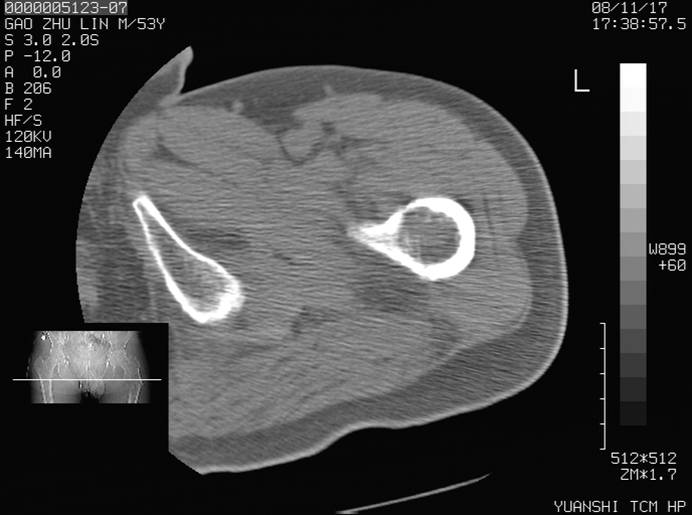

标题: CT16696:M53Y,左股骨上段骨折。 [打印本页]

标题: CT16696:M53Y,左股骨上段骨折。

左股骨上段外伤1个小时,左股骨上段疼痛。村医以腰椎间盘病变给以按摩及理疗数天。

图像不太清楚,左股骨上段外伤性骨折?病理性骨折?

左股骨上段粉碎性骨折

左股骨上段粉碎性骨折;建议上传骨窗看看是不是病理性的啊!

左股骨上段粉碎性骨折,不排除病理性骨折可能。

考虑骨肉瘤伴病理骨折

病理性骨折,考虑转移所致.